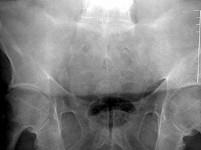

男,48岁,背痛,四肢强直,请结合影像图像,选择最可能的诊断 ( )A、骨脓肿B、骨软骨瘤C、压缩性骨折D、骨囊肿E、强直性脊柱炎

问题 男,48岁,背痛,四肢强直,请结合影像图像,选择最可能的诊断 ( )

选项 A、骨脓肿 B、骨软骨瘤 C、压缩性骨折 D、骨囊肿 E、强直性脊柱炎

答案 E